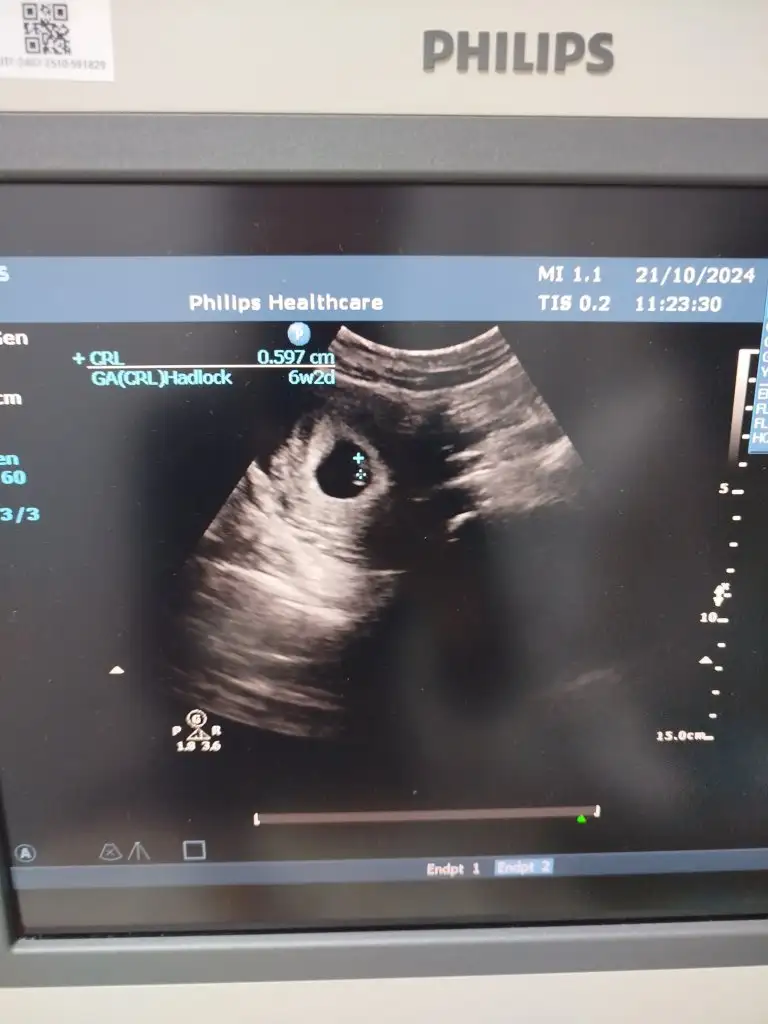

5 ve 14. haftaya kadar olan ultrason fotolarınızı paylaşın. Vajinadan mı yoksa karından mı çekildiğini ve kaç haftalık olduğunu da mutlaka belirtin.